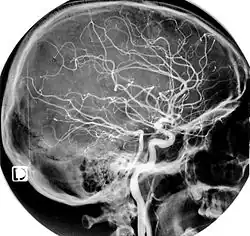

L'artère carotide interne et ses branches contribuent à la formation du polygone de Willis, anastomose avec les artères homologues (du côté opposé) et celles issues de l'artère basilaire.